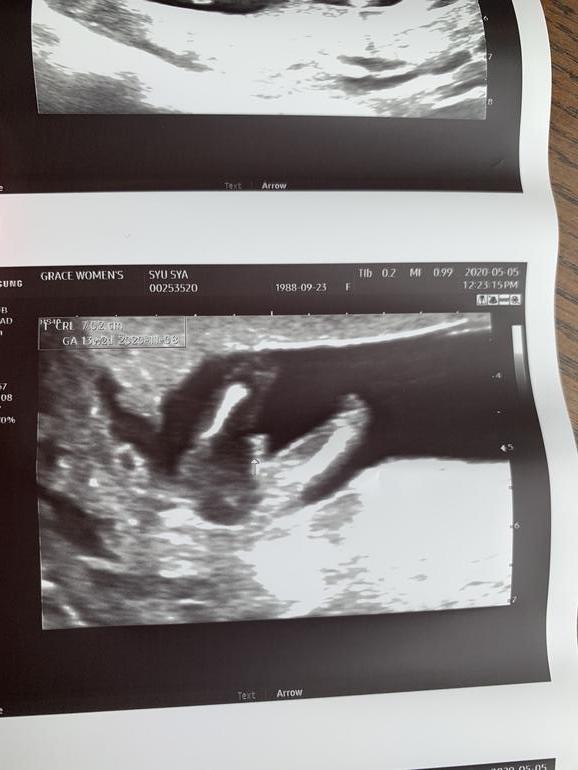

До 11 недель ходили в одну клинику, а сейчас решили поменять. Пришли на УЗИ, и врач очень уверено говорит, что мальчик. Даже фото показал🙈😅 Вот теперь думаю, насколько это точно.